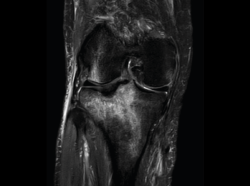

4.3. Osteocondritis

En la osteocondritis se aprecia una lesión subcondral caracterizada por resorción ósea, colapso y la formación de un secuestro.

El estudio por RM es una herramienta valiosa para diagnosticar e identificar las lesiones del cartílago. Conocer el aspecto del cartílago y saber cuánto y cuándo se lesiona, basándose en las clasificaciones actuales, permiten al radiólogo proporcionar la máxima información al clínico(20).

Numerosos estudios demuestran la utilidad de la RM para definir la estabilidad o inestabilidad de la lesión en la osteocondritis, destacando su carácter no invasivo y la capacidad de valorar la progresión y la respuesta al tratamiento(21)(Figuras 53 y 54).